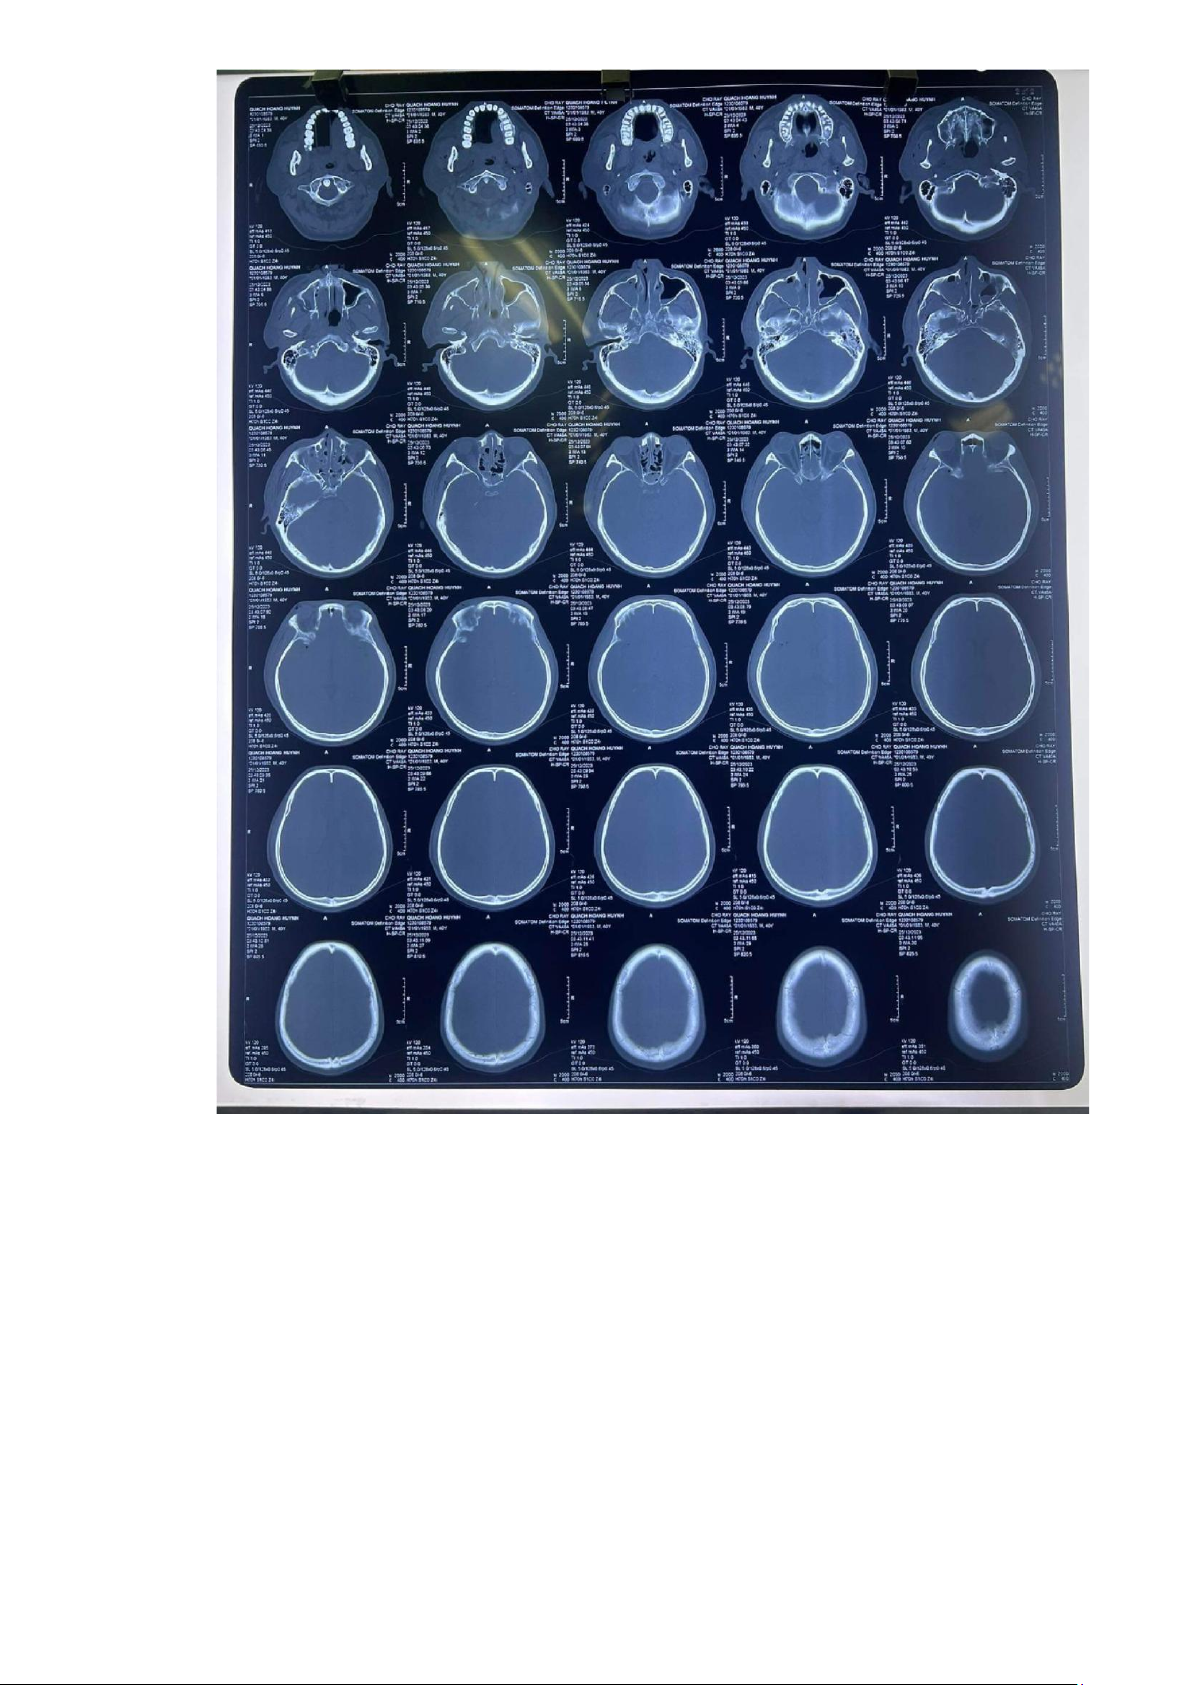

5. CTScan sọ não (25/12/2023 tại cấp cứu bv Chợ Rẫy):

• Không thấy máu tụ nội sọ

• Tụ khí nội sọ rải rác lOMoAR cPSD| 45469857

• Nứt sọ thái dương (P)

• Gãy xương hàm trên (P)

• Gãy thành ngoài hốc mắt, cung gò má, gãy thành xoang hàm (P), xoang bướm hai bên

• Tụ máu các xoang cạnh mũi

• Phù nề, tụ máu mô mềm hàm mặt, quanh mắt (P) lOMoAR cPSD| 45469857 lOMoAR cPSD| 45469857

Chụp lại CT scans sọ não 27/12/2023 (2 ngày sau chấn thương) Kết luận:

Tụ máu ngoài màng cứng vùng trán-đính (P)

Tụ máu dưới màng cứng lớp mỏng vùng trán (P) dọc lều tiểu não

Dập não xuất huyết trán (P), thái dương (P)

Xuất huyết dưới nhện rải rác bán cầu (P), não thất bên (P) bị chèn ép và di lệch đường giữa qua (T) nhẹ

Nứt sọ đính 2 bên trán (P) lOMoAR cPSD| 45469857

Dãn nhẹ đường khớp vành